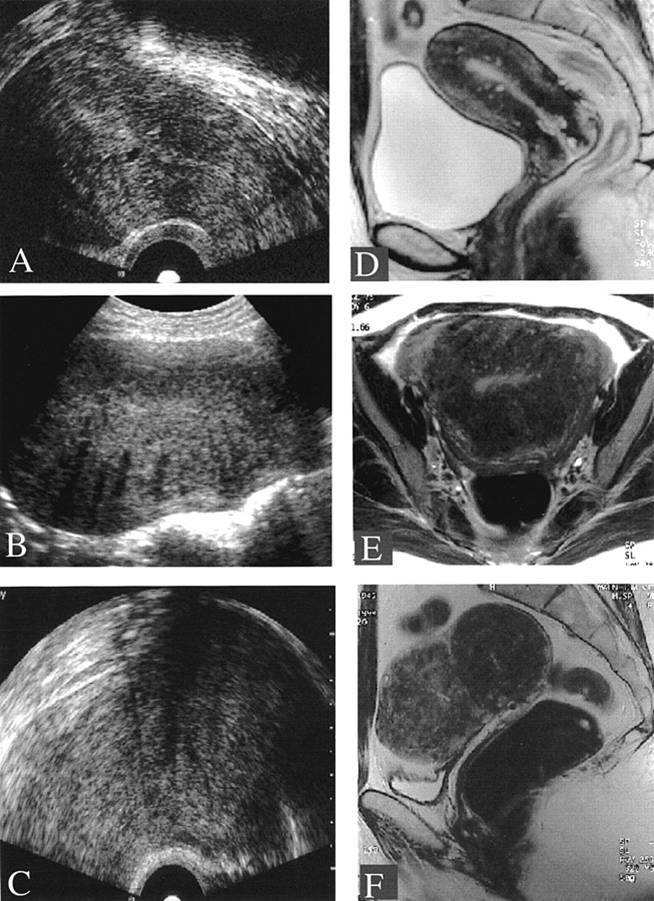

Fondamentale risulta quindi essere la diagnostica per immagini, in particolare l'indagine ecografica che, mediante il più preciso approccio trans-vaginale, permette uno studio accurato dell'apparato genitale. L'osservazione degli annessi può rivelare, nel loro contesto, la presenza di una cisti caratteristica per il contenuto ipoecogeno finemente corpuscolato, le pareti lisce a profilo regolare, e la bassa vascolarizzazione allo studio Color-Doppler. La presenza di un miometrio dall'aspetto disomogeneo, di cripte ghiandolari non vascolarizzate nel suo contesto, o di una giunzione endometrio-miometrio irregolare, è suggestiva di adenomiosi (3) (fig 1, 2A-B).

Figura 1: Immagine ecografica di cisti endometriosica dell'ovaio

Figura 2 A: Immagine ecografica di adenomiosi. Le frecce indicano isole di tessuto endometriale che invadono il miometrio

Figura 2 B: Rappresentazione schematica delle localizzazioni di adenomiosi nel contesto del miometrio.

Un ulteriore aiuto diagnostico può derivare dalla risonanza magnetica (RM), che riconosce le lesioni endometriosiche pelviche grazie alla presenza di prodotti di degradazione del sangue al loro interno (risultando iperintense in T1 e ipointense in T2) (4) (fig 3).

Figura 3: Confronto tra immagini ecografiche (a sinistra) e RMN (a destra) di adenomiosi; si notino gli spot iperintensi in T1 nel contesto del miometrio (D).